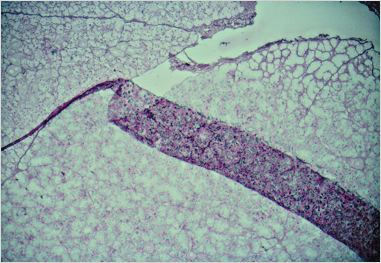

Pli (diapo 5)